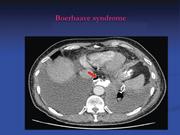

A delayed presentation of Boerhaave's syndrome with mediastinitis managed using the over-the-scope clip

Eamon Ramhamadany and others

Journal of Surgical Case Reports, Volume 2013, Issue 5, May 2013, rjt020, https://doi.org/10.1093/jscr/rjt020